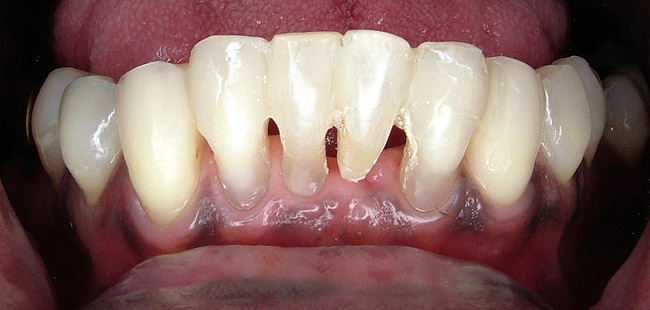

When fiber-reinforcing materials were introduced, the focus for their use was for periodontal splinting and stabilization resulting from tooth mobility.6,10,16,41-43 There is no doubt that splinting does reduce tooth mobility while the splint is in place.44 In the last decade, research supports the use of periodontal splinting as recommended therapy to stabilize those teeth to improve long-term prognosis.45-47 In a long-term clinical evaluation of splinting over a period of 48 to 96 months, using the original Ribbond Reinforcement Ribbon in fiber-reinforced composite resins was highly successful.17 The success of these splints can be attributed to close adaptation of the fiber ribbon to the tooth surface combined with cross stabilization of the mobile teeth by placing adhesive composite resin on the facial surfaces (Figure 4A, Figure 4B, Figure 4C, Figure 4D, Figure 4E).34,35 Splinting of traumatized teeth with fiber-reinforcing materials and adhesive composite resin has also been reported.48,49 When using fiber to stabilize the traumatized tooth or teeth or for tooth stabilization after re-implantation, the tooth must be allowed to have some movement and not be fixed in place.50,51